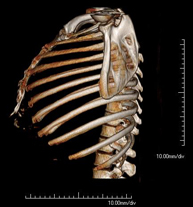

Exploración radiológica que mediante un sistema de rayos X y detectores que giran alrededor del paciente, reconstruyendo las imágenes por ordenador, permite el estudio detallado de la parrilla costal. - Angio-TC Cardíaco o TC Cardíaco

Exploración radiológica que mediante un sistema de rayos X y detectores que giran alrededor del paciente, reconstruyendo las imágenes por ordenador, permite el estudio detallado del esternón. - TC Clavículas

Exploración radiológica que mediante un sistema de rayos X y detectores que giran alrededor del paciente, reconstruyendo las imágenes por ordenador, permite el estudio detallado de las clavículas. - TC Parrilla costal